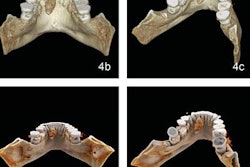

Cinematic rendering of an abdominal CT scan.In the current article, the group discussed three distinct ways in which cinematic rendering could facilitate the evaluation of a variety of conditions affecting the spleen, including the following:

- Vascular conditions: Cinematic rendering is particularly well suited for visualizing vasculature near the hilum of the spleen, an area frequently affected by stomach and pancreatic tumors that restrict blood flow to certain parts of the spleen. Cinematically rendered CT scans display clear demarcations between these infarcted regions and otherwise stable areas.

In addition, the advanced visualization technique clearly depicts textural changes and fluid leakage in the spleen commonly associated with lacerations in trauma patients. These findings may additionally be able to help predict a patient's need for splenectomy.

- Neoplastic processes: The intrinsic ability of cinematic rendering to accentuate texture enables it to reveal spleen lymphomas, the organ's most common malignancy, more readily than standard CT -- thereby facilitating cancer diagnosis and prognosis, the authors noted. For rare tumors such as littoral cell angiomas, cinematic rendering can pinpoint underlying abnormalities that may help physicians distinguish between benign and malignant cases.